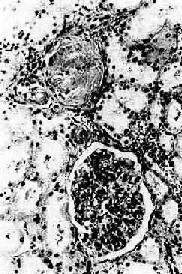

图8-11 高血压病时左心室向心性肥大(心脏横断面) 左心室壁增厚,乳头肌显著增粗 3.肾的病变 表现为原发性颗粒性固缩肾,为双侧对称性、弥漫性病变。 肉眼观,肾体积缩小,质地变硬,重量减轻,一侧肾重量一般小于100g(正常成年人一侧肾重约为150g)。表面布满无数均匀的红色细颗粒。切面,肾皮质变薄,一般在2mm左右(正常厚3~5mm)。髓质变化不明显,但肾盂和肾周围脂肪组织明显增生。 镜检下,肾细动脉硬化明显,小叶间动脉及弓形动脉内膜增厚。依病程而有多少不等的入球动脉及肾小球发生玻璃样变(图8-12)。附近的肾小管由于缺血而萎缩、消失,间质结缔组织增生及淋巴细胞浸润。该处由于肾实质萎缩和结缔组织收缩而形成凹陷的固缩病灶,周围健存的肾小球发生代偿性肥大,所属肾小管亦呈代偿性扩张,使局部肾组织向表面隆起,形成肉眼所见的无数红色细颗粒(由于该处血供良好而呈红色)。

图8-12 高血压病之肾 肾小球入球小动脉管壁玻璃样变性,肾小球纤维化,玻璃样变 临床上,可多年不出现肾功能障碍。晚期由于病变的肾单位越来越多,肾血流量逐渐减少,肾小球滤过率逐渐降低。患者可发生水肿、出现蛋白尿及管型。严重者可出现尿毒症的临床表现。 4.脑的病变 高血压时,由于脑内细动脉的痉挛和病变,患者可出现不同程度的高血压脑病(hypertensive encephalopathy)症状,如头痛、头晕、眼花等,甚至出现高血压危象。患者有明显的中枢神经症状,如意识模糊、剧烈头痛、恶心、呕吐、视力障碍及癫痫发作等。 (1)脑动脉病变:严重的病例细动脉和小动脉管壁可发生纤维素样坏死,可并发血栓形成及微动脉瘤(microaneurysm)。后者好发于壳核、丘脑、脑桥、小脑和大脑,这些部位也是高血压性脑出血及脑梗死发生率最高之处。 (2)脑软化:由于细动脉、小动脉病变造成其所供养区域脑组织缺血的结果,脑组织内可出现多数小软化灶,即微梗死灶(microinfarct)。镜检下,梗死灶内脑组织坏死液化,形成染色较浅、质地疏松的筛网状病灶。灶内可见坏死的细胞碎屑,周围有胶质细胞增生及少量炎性细胞浸润。最后,坏死组织被吸收,由胶质瘢痕修复。由于软化灶较小,一般不引起严重后果。 (3)脑出血:是高血压最严重的且往往是致命性的并发症。多为大出血灶,常发生于基底节、内囊,其次为大脑白质、脑桥和小脑。出血区域的脑组织完全被破坏,形成囊腔状,其内充满坏死的脑组织和凝血块。有时出血范围甚大,可破入侧脑室(图8-13)。引起脑出血的原因一方面由于细、小动脉的病变,另一方面,脑出血多发生于基底节区域(尤以豆状核最多见),供养该区的豆纹动脉从大脑中动脉呈直角分出,直接受到大脑中动脉压力较高的血流冲击,易使已有病变的豆纹动脉破裂出血。此外,血压突然升高(如情绪激动时)亦易使病变的动脉破裂出血。临床上,患者常骤然发生昏迷、呼吸加深和脉搏加快。严重者可发生陈-施(Cheyne-Stokes)呼吸、瞳孔反射及角膜反射消失、肢体弛缓、肌腱反射消失、大小便失禁等症状。出血灶扩展至内囊时,引起对侧肢体偏瘫及感觉消失。出血灶破入侧脑室时,患者发生昏迷,常导致死亡。左侧脑出血常引起失语,脑桥出血可引起同侧面神经麻痹及对侧上下肢瘫痪。